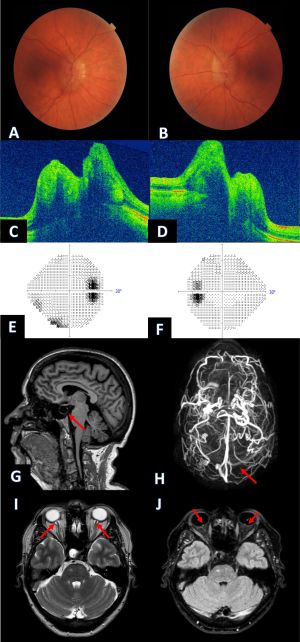

Upon ocular examination, papilledema is the hallmark sign of IIH. It is typically bilateral and symmetric, however unilateral or asymmetrical cases may also occur. The Frisén scale may be used to grade severity of the papilledema. However, the literature describes a few cases of IIH without papilledema among patients presenting with intractable headache and elevated opening pressure on lumbar puncture.

The following may also be present on fundoscopic examination: choroidal compression across macula, choroidal neovascularisation, and retinal elevation around optic nerve head. Finally, 6th cranial nerve palsy may be present as a non-localizing sign of increased intracranial pressure.

When evaluating a patient for IIH, a complete ocular examination including a dilated fundus examination, visual field examination, and optic nerve photographs is required. Subsequently, neuroimaging is needed to exclude secondary causes of intracranial hypertension. Magnetic resonance imaging (MRI) and MR venography (MRV) of the brain are usually the imaging modalities of choice. It may show abnormalities suggestive of IIH that are however not specific as they may be seen with other causes of increased ICP. The findings include:

- Flattening of the posterior pole

- Empty/partial empty sella

- Enhancement (with gadolinium) of the prelaminar optic nerve

- Distension of perioptic subarachnoid space

- Vertical tortuosity of the orbital optic nerve

- Intraocular protrusion of the prelaminar optic nerve

- Stenosis of one or both transverse cerebral venous sinuses